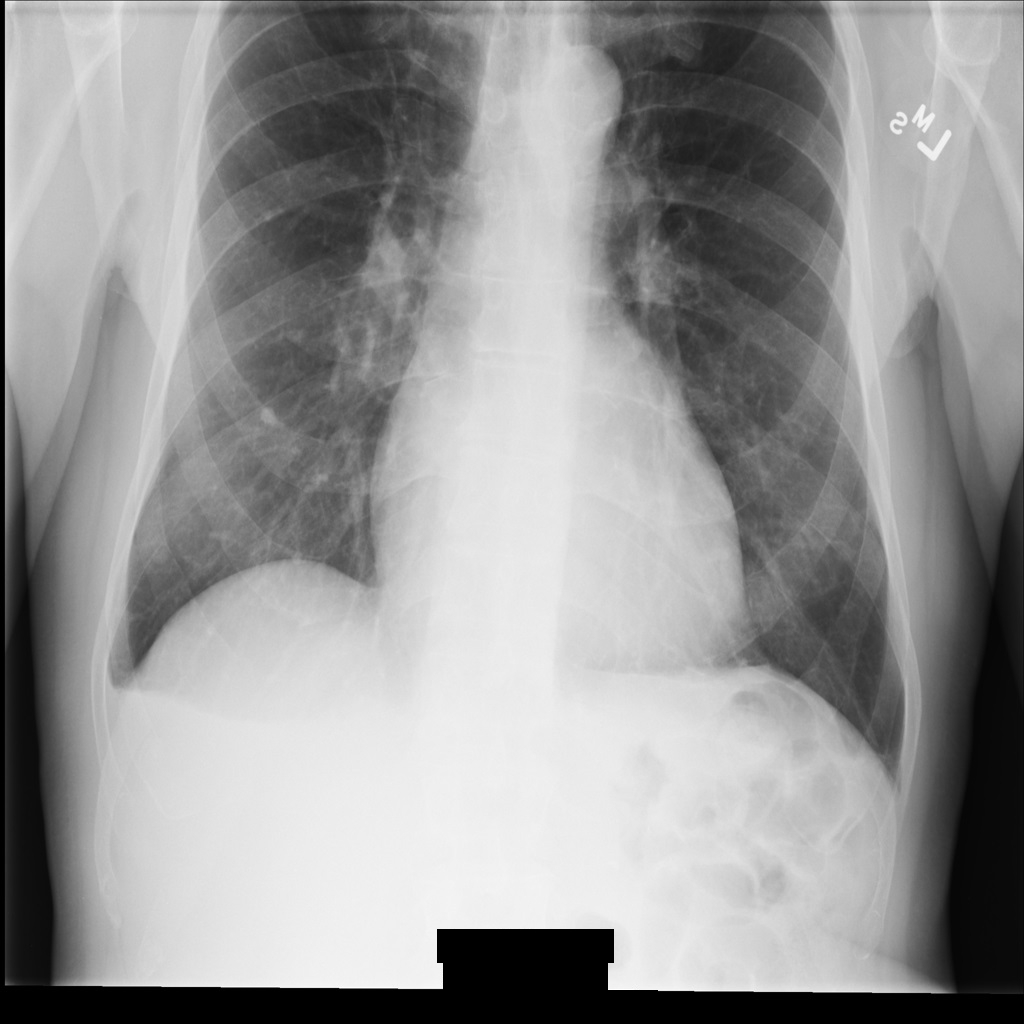

Imagen de muestra

Algunas muestras de esta página contienen el resultado de la imagen anonimizada. En cada ejemplo se usa la siguiente imagen original como entrada. Puedes comparar la imagen de salida de cada operación de anonimización con esta imagen original para ver los efectos de la operación: